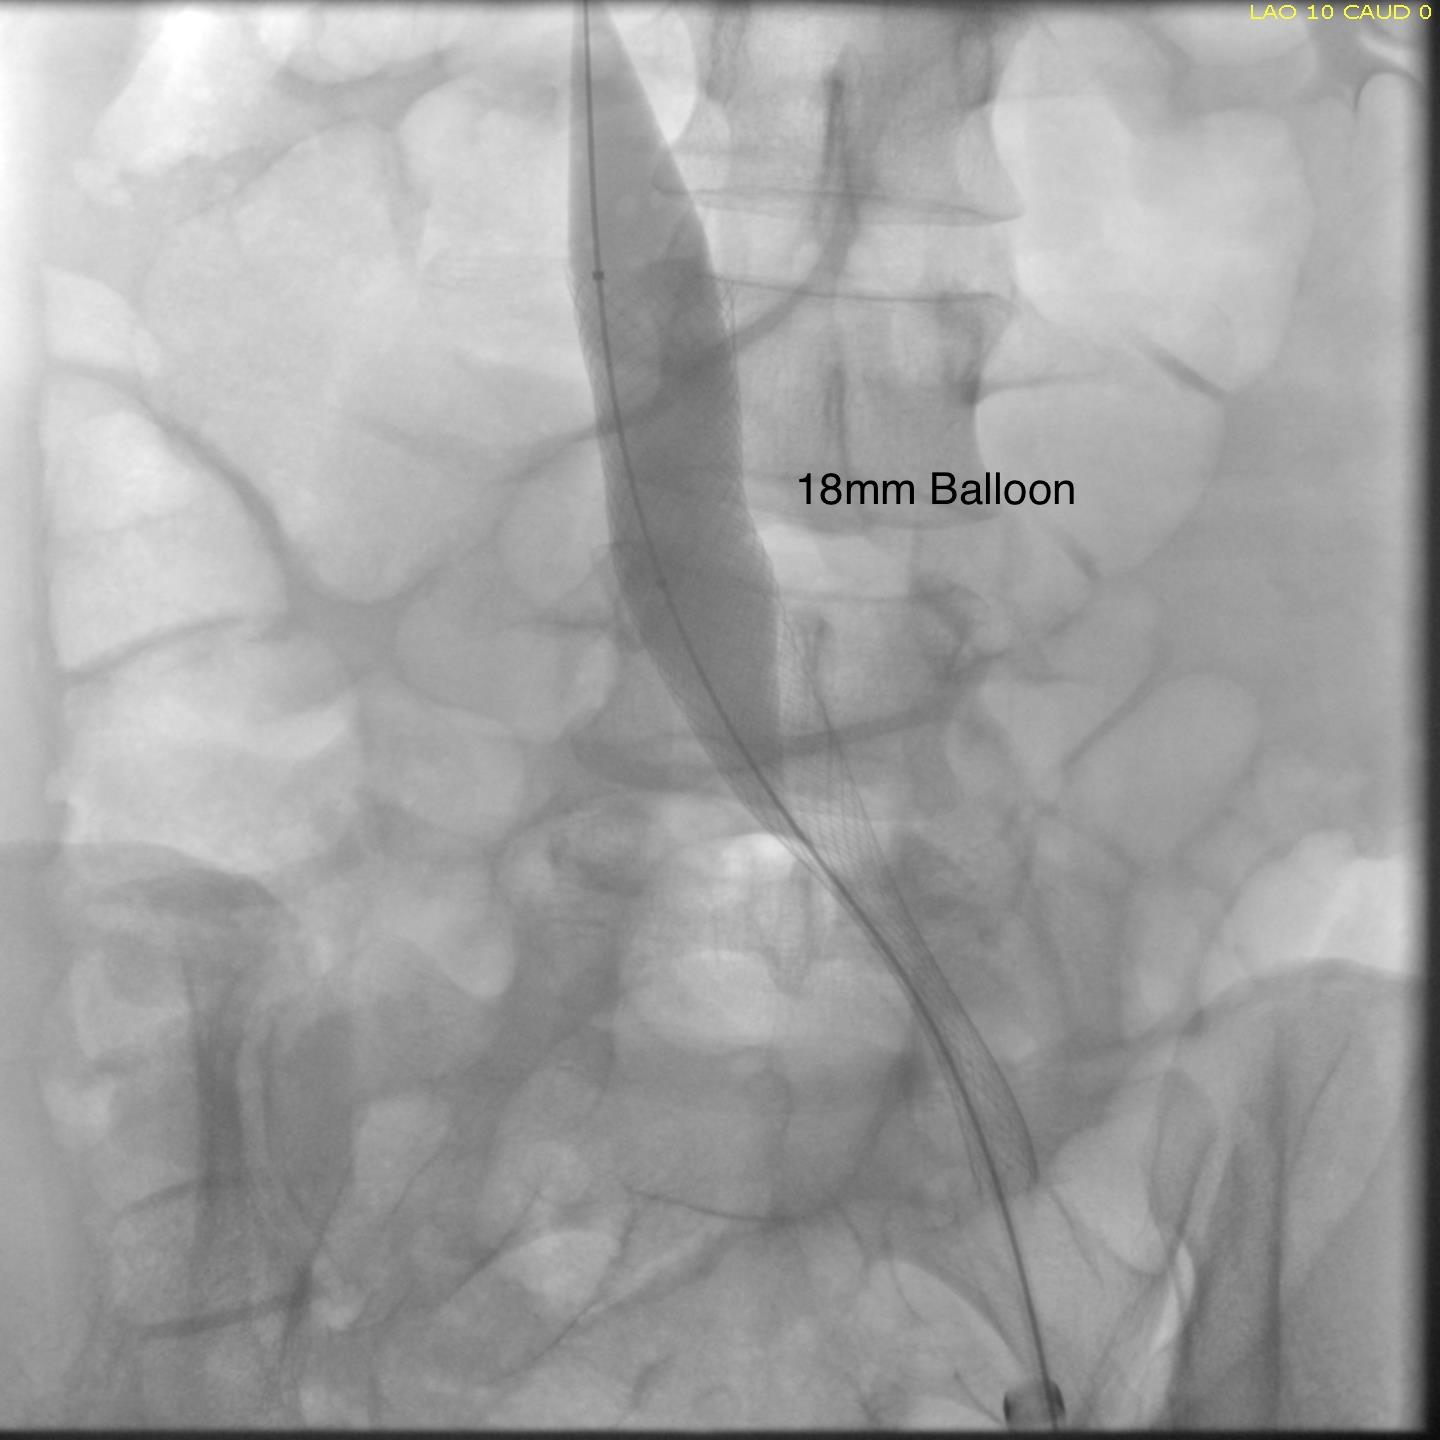

Once this is done, the iliac veins are dilated to 14mm from the IVC to the common femoral arteries. large 18mm Wall stents are deployed in a kissing fashion from the caval stent into both iliac systems and dilated to 18mm.

intervention fig 6.png

Predilatation of iliac venous systems with ever larger balloons, deployement of bilateral 18mm Wall Stents

After deployment, the Wall Stents are ballooned to 18mm. These stents were extended into the common femoral artery with 14mm nitinol stents.

intervention fig 7.png

Ballooning 18 mm Wall Stents with 18mm Atlas balloons, then extending to CFA with nitinol stents of 14mm

Completion venography suggested successful iliocaval recanalization and revascularization but these procedures are not done without a final intravascular ultrasound (IVUS).

Looks done, but needed final intervention after IVUS.

Intravascular ultrasound revealed incomplete expansion of the right common femoral stent. This was treated with another stent and ballooning with the result on the right.

Stent compression on IVUS treated with second stent

Venography alone is insufficient in determining patency. As illustrated, IVUS ensures a durable outcome.